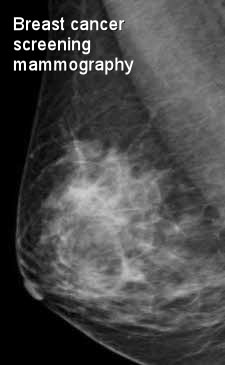

Что такое маммография: важность, процесс и результаты